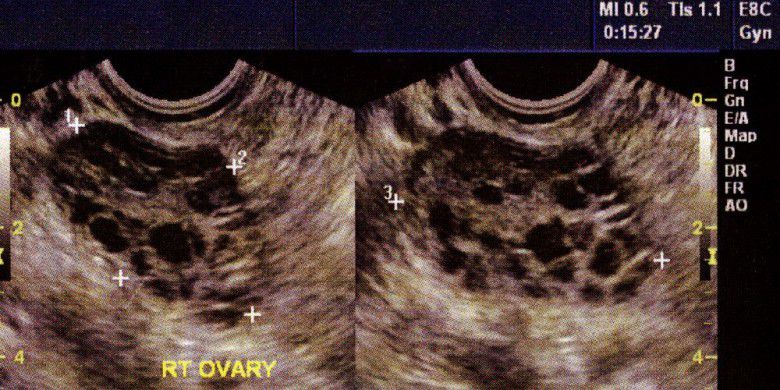

Kantung-kantung atau folikel pada penderita PCOS (womenshealthmag.com)